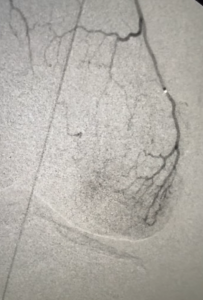

GAE is a non-surgical, image-guided procedure that reduces inflammation by blocking the tiny blood vessels (genicular arteries) responsible for supplying excess blood flow to the inflamed areas of the knee joint.

During the procedure, an interventional radiologist inserts a small catheter, typically through the wrist or groin, and releases microscopic particles to limit this abnormal blood flow.